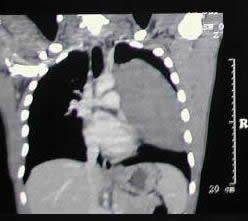

un paciente joven, con un gran tumor del mediastino anterosuperior de rápido

crecimiento, correlacionando su tamaño entre la radiografía

del tórax y los hallazgos tomográficos realizado 15 días

después, y las condiciones físicas al momento de su intervención,

con gran dificultad respiratoria.